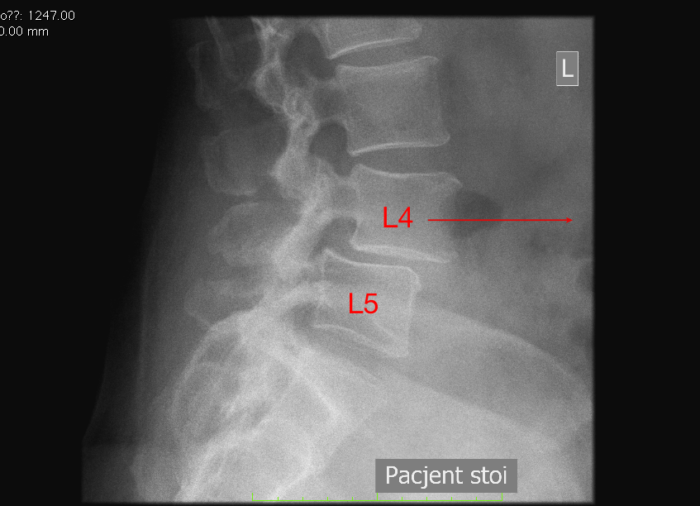

Kręgozmyk segmentu L4-L5, czyli translatoryczne przemieszczenie się kręgu L4 względem poniżej leżącego L5.